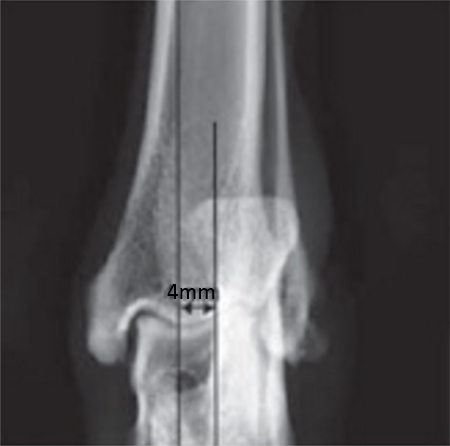

Case 1: Two-year-old Labrador Retriever

2-years-old Labrador Retriever, 30 kg, female. Chronic lameness in both hind limbs, chronic bilateral cranial cruciate ligament tears, with subsequent stifle joint instability and degenerative joint disease. At that time, she was more clinically lame on the left hind limb, and a surgical correction was subsequently performed on this limb. X-rays of the stifle joint revealed the degenerative joint changes and an effusion; the tibial plateau slope was 20. In addition, the x-rays confirmed that there was a slight amount of tibial torsion that also was observed clinically, accounting for a slight internal rotation of the distal limb. Radiographically, this could be assessed by a 4 mm shift of the normal point of intersection of the medial aspect of the calcaneus with the deepest point of the talar sulcus.